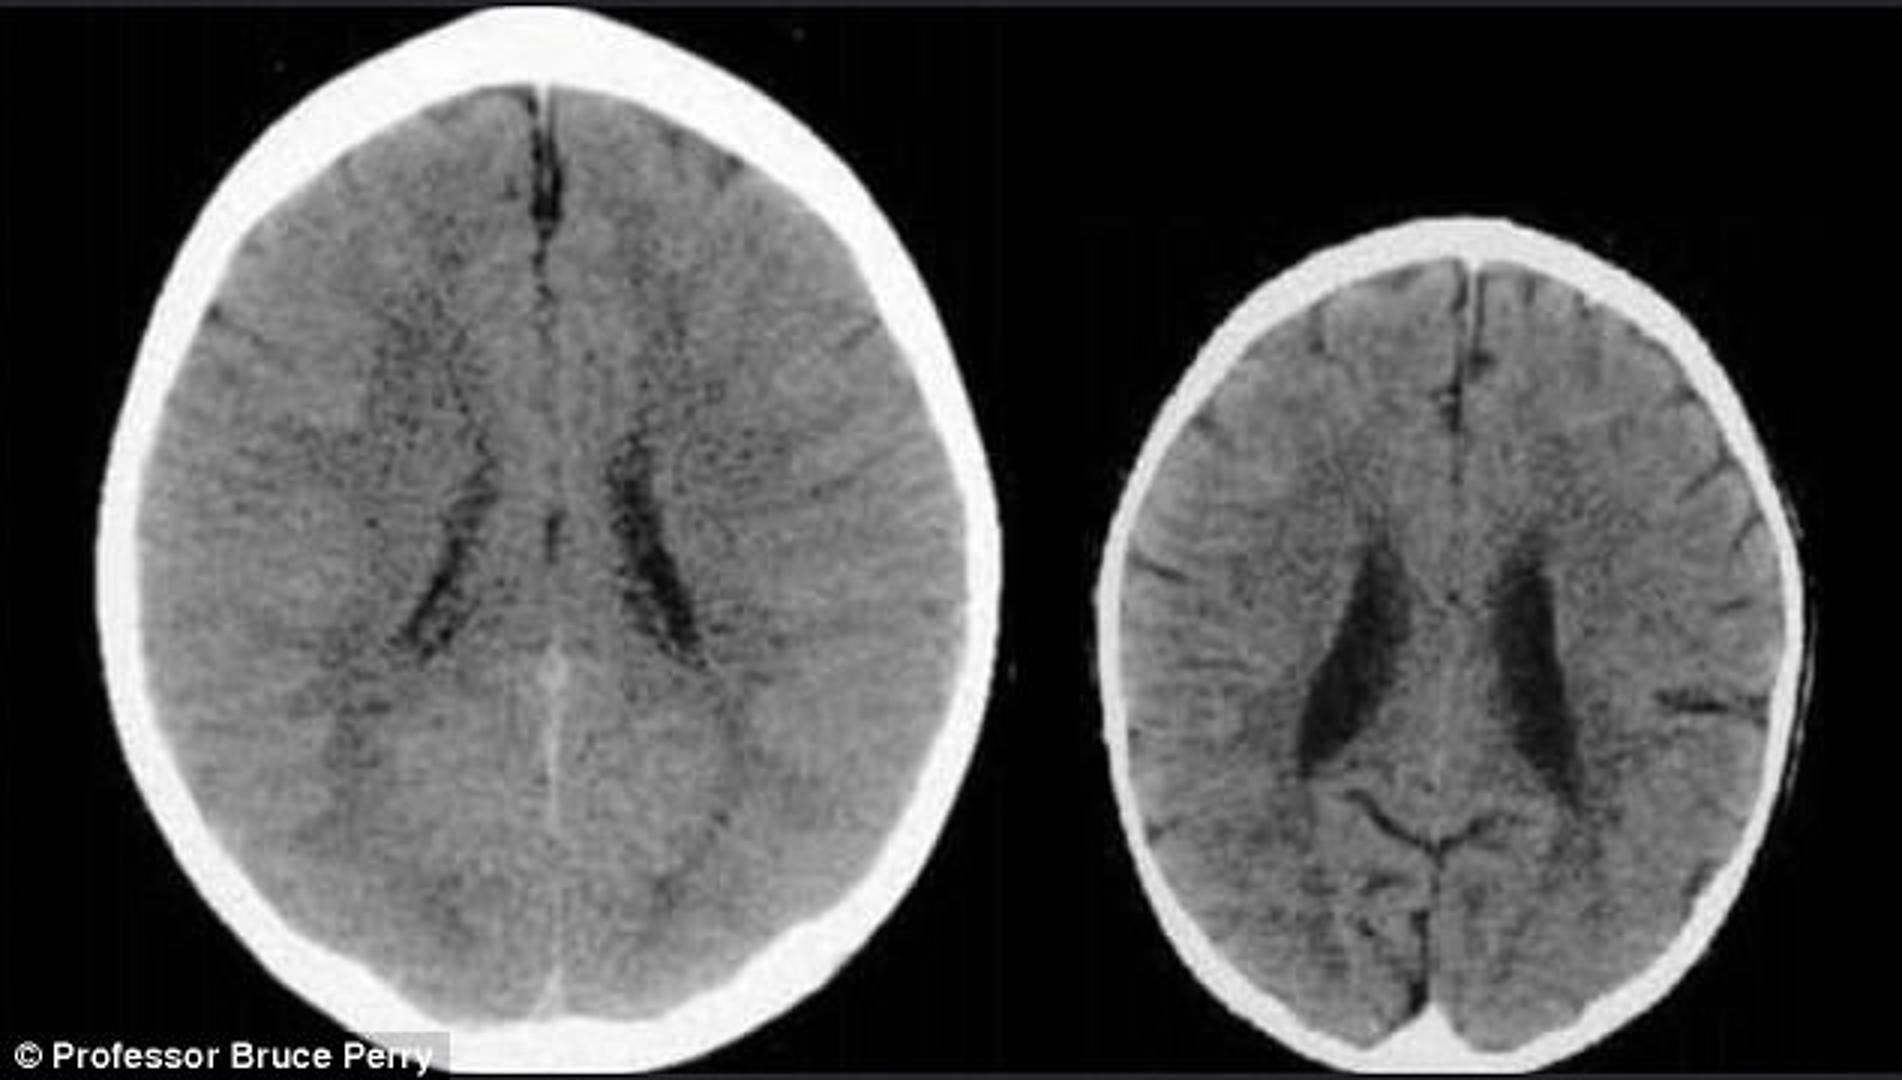

Snimke mozgova dvaju djeteta pokazala su šokantne razlike. Podijelio ih je Bruce Perry, glavni psihijatar u teksaškoj bolnici.

Lijeva snimka pokazuje dijete koje je odraslo u okruženju koje ga je poticalo i ohrabrivalo, dok je desna snimka ona djeteta koje je bilo zanemarivano.

Ne samo da je mozak zlostavljanog djeteta manji, već su njegovi dijelovi na CT snimci puno mutniji.

- Ove snimke ilustriraju negativan utjecaj zanemarivanja na mozak u razvoju - zaključuje Perry.